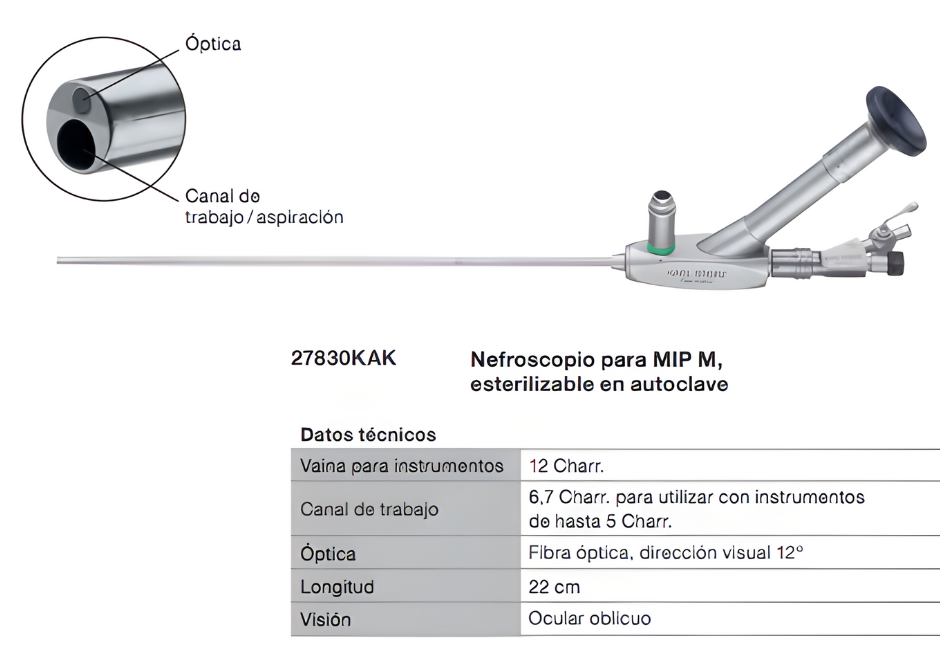

Nefroscopio

Telescopio Panoview con ocular desplazado lateralmente, dirección de visión de 12° y canal de trabajo de 6 Fr.